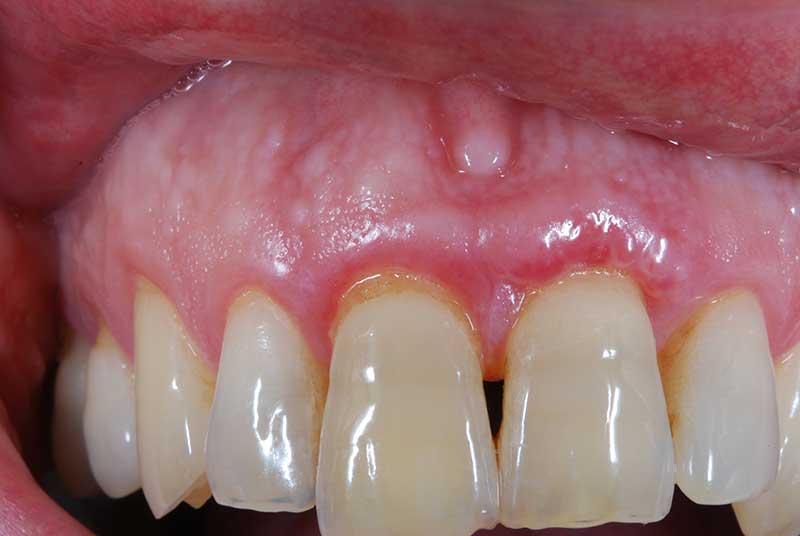

Con protesi fissa superiore e protesi fissa inferiore

sono stati sostituiti da 10 impianti, cioè protesi radicolari endo-ossee che sostengono le protesi fisse superiore ed inferiore.